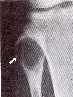

• Radiología:

Lesión lítica expansiva con cortical adelgazada

• Histología: Células Gigantes + fibroblastos